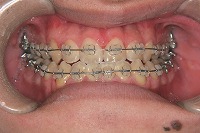

反対咬合と下顎が出ている事を主訴に来院された、初診時18歳1か月の男性です。診断「上顎骨の後方位による骨格性反対咬合」非抜歯での矯正治療と、下顎を後退させる外科手術を併用して治療を行いました。

正面